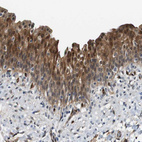

Immunohistochemistry analysis in human urinary bladder and liver tissues using HPA014179 antibody. Corresponding LXN RNA-seq data are presented for the same tissues.